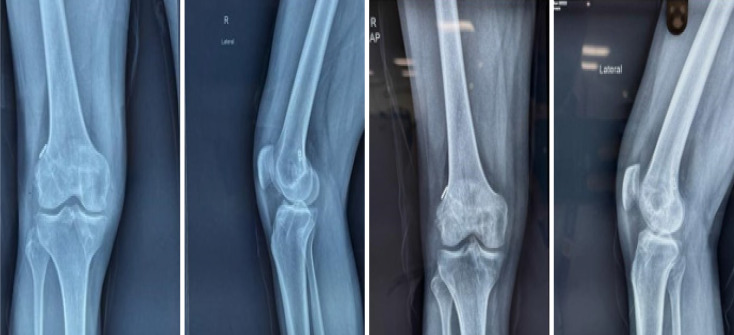

Case summary: A 26-year-old male presented with knee pain and swelling one year after ACL reconstruction using a hamstring graft and bioabsorbable tibial interference screw. The patient had been engaged in rigorous physical activity as part of military training. Clinical examination revealed mild effusion without instability, and imaging showed screw breakage with intra-articular migration. Therapeutic arthroscopy confirmed intact graft tension, and broken screw fragments were removed successfully. The patient resumed normal activity two weeks after surgery.